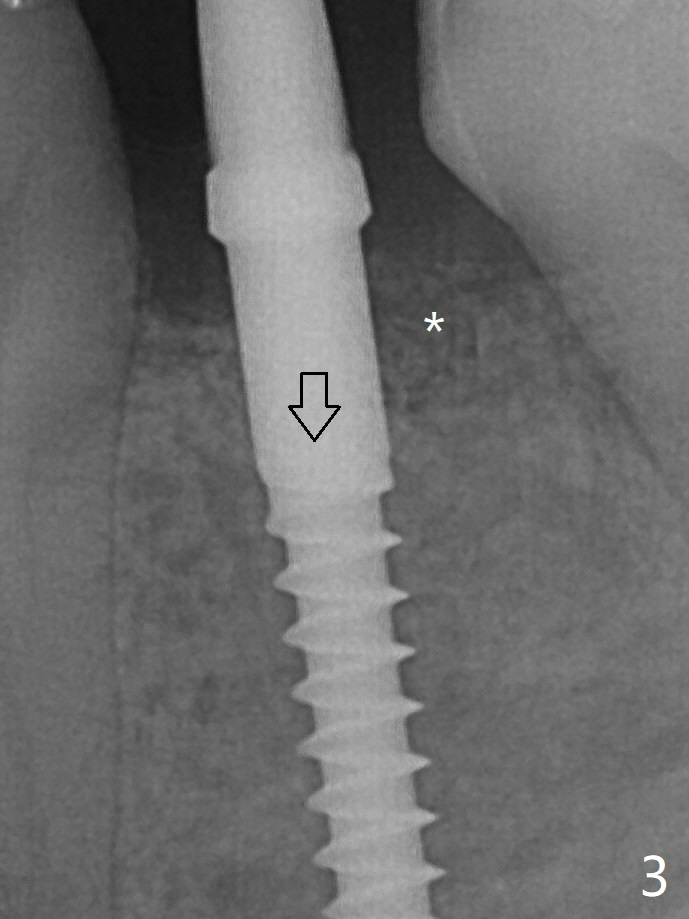

With the implant placed a little deeper (Fig.3 arrow), bone graft is placed (*), followed by suture. There is no bone loss with retention of bone graft 4 months postop; after reprep of the neighboring teeth, impression is taken (Fig.4). The three crowns are cemented 4.5 months postop (Fig.5).